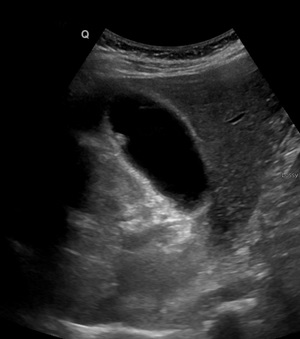

| |

|

Adenome pedicule

de forme tubulaire . Aspect de adenomeme est

isoechogenique colletant au paroi par une pedicule .

Image echographique en coupe longitudinale de la

vesicule biliaire |

Image de

adenomateuse polyppoide isoechogenes de type sessile

: Image echographique en coupe longitudinale de la